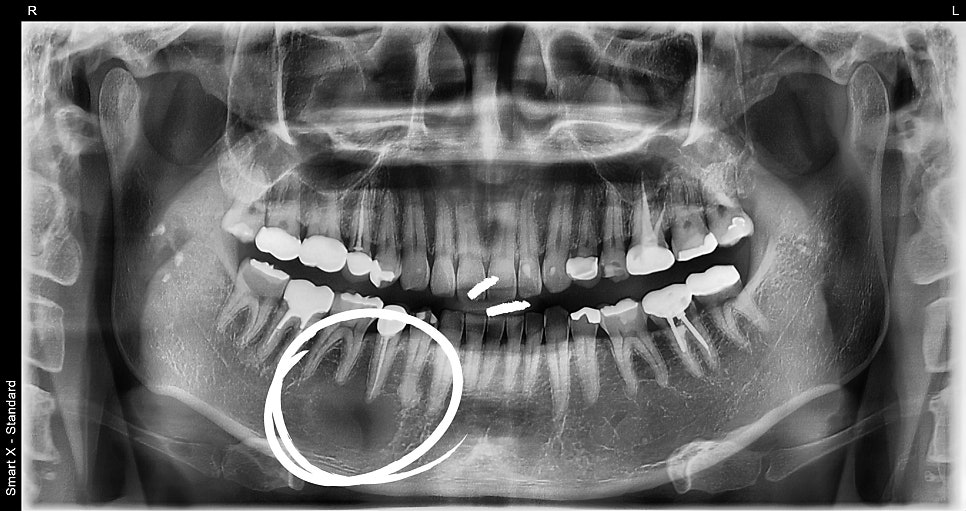

파노라마 촬영 및 CBCT(3D CT) 검사 결과,

해당 부위 하악골 내에 경계가 명확한 방사선 투과성 병소가 확인되었습니다.

진단 결과: 하악골 내 양성종양 의심 병소 병소는 약 2.5cm 크기의

원형 낭성 병변 염증과는 달리 주변 조직과 구분되는 경계성 병소

감별진단: 치근단 낭종 / cementoblastoma / odontogenic tumor 등 가능성

→ 확정 진단 위해 병소 조직 절제 및 생검(조직검사) 필요

📸 수술 전

– 치근단 부위에 낭종성 병소